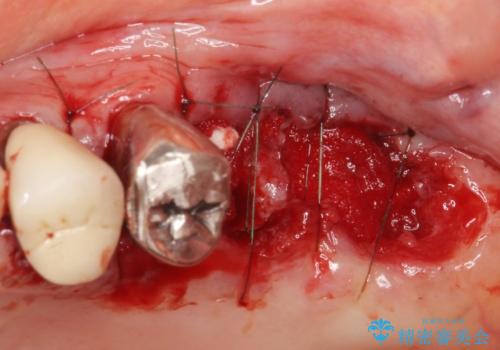

「抜歯したくない、インプラントは嫌」という患者様のご希望とご年齢を考慮し、可及的な骨外科処置や根分割術によりできるだけ今ある歯を残す治療方針をたてました。

保存不可能な左上の奥歯2本(左上67)は抜去し、ノンクラスプデンチャーをいれることにしました。

- 外科手術のため、術後に痛みや腫れ、違和感を伴います

- 歯周組織再生治療は患者様の状態によって術後の経過が異なります(見た目が改善しない場合もあります)